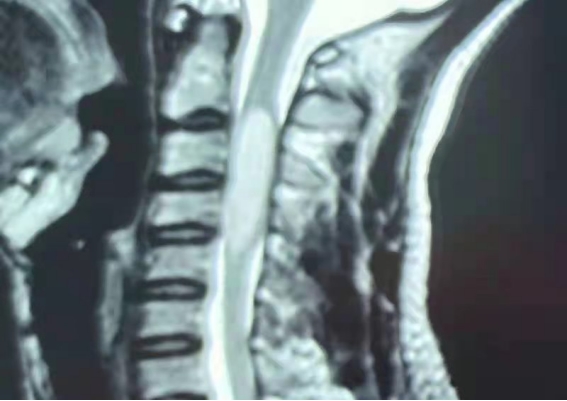

患者,男,26岁,因右上肢活动受限2月入院治疗。颈椎核磁平扫及强化检查明确有颈段髓内占位性病变(颈2-颈5)。

术前核磁平扫